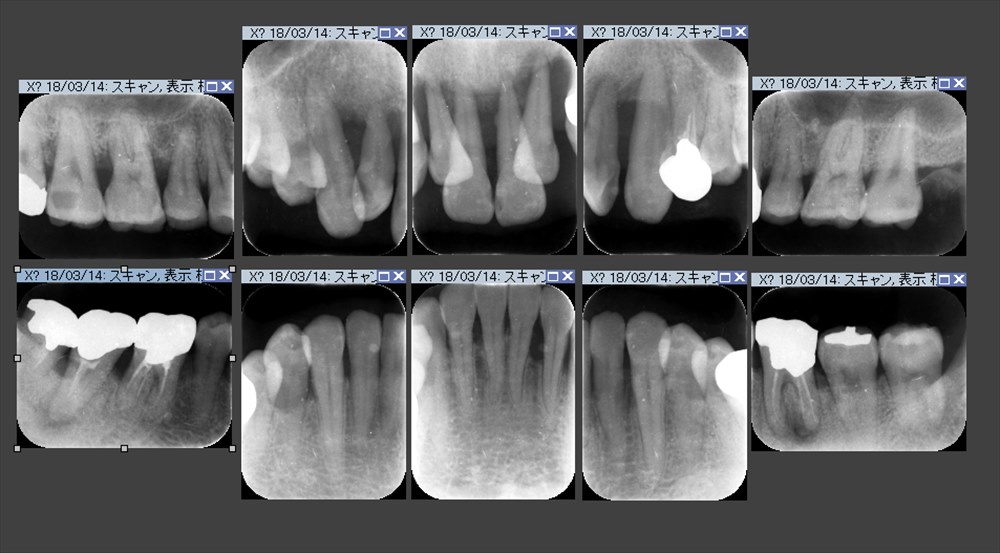

その時のレントゲンです。

不思議です。見る人が見ると分かると思いますが右上、右下で骨の再生が見られます。

この治療も歯周病の再生手術をしておりません。

再生材料も全く使用しないレーザーのみの基本治療のみです。

血餅が安定するように治療しています。

日付をみて頂くとお分かりになるかと思いますが歯周基本治療に約1年掛かっています。